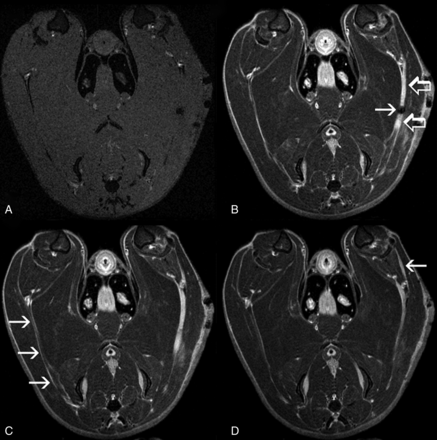

Qualitatively, 14 of 14 (100%) forceps-injured nerves demonstrated avid Gd-DTPA enhancement on T1WI. Enhancement was seen a few millimeters proximal to, in the region of, and several centimeters distal to the site of crush injury (Fig 3). Like T2 signal hyperintensity, Gd-DTPA enhancement extended distally into the tibial and peroneal nerve branches. However, Gd-DTPA enhancement did not extend as far proximally (toward the sciatic notch) as T2 signal hyperintensity. Robust Gd-DTPA enhancement was observed in forceps-injured nerves as early as 3 days after injury. Enhancement peaked at 7 days and subsequently diminished, but it was still evident on day 21 (Fig 4).

Axial T1WI with fat saturation, pre- (A) and post- (B–D) Gd-DTPA (same animal as in Fig 2). A, On precontrast images, both injured and nonoperative nerves are isointense to muscle. B, Intense Gd-DTPA enhancement (open arrows) is demonstrated a few millimeters proximal to, in the region of, and distal to the site of crush injury (arrow) (On-line Video 1). C, The nonoperative contralateral nerve (arrows) is well seen in this section and demonstrates a thin rim of peripheral enhancement but no internal enhancement (On-line Video 2). D, Enhancement is seen in a distal branch (arrow) of the injured sciatic nerve (On-line Video 3).